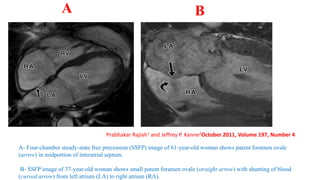

A- Four-chamber steady-state free precession (SSFP) image of 61-year-old woman shows patent foramen ovale

(arrow) in midportion of interatrial septum.

B- SSFP image of 37-year-old woman shows small patent foramen ovale (straight arrow) with shunting of blood

(curved arrow) from left atrium (LA) to right atrium (RA).

A B

Prabhakar Rajiah1 and Jeffrey P. Kanne2October 2011, Volume 197, Number 4